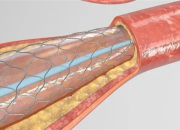

对于肾脏,大家可能是既熟悉又陌生,它是人体的重要器官,负责过滤血液中的废物、调节水分和电解质平衡、维持血压和产生红细胞等。慢性肾病(CKD)是全球重要的公共卫生问题,影响超过8.5亿人,数据表明,预计到2040年,慢性肾病将成为全球导致预期寿命缩短的第五大病因。慢性肾病早期往往没有明显症状,因此容易被忽视,当肾脏功能严重受损时,可能会导致肾衰竭,甚至需要透析或肾移植来维持生命。根据中国医师协会肾脏